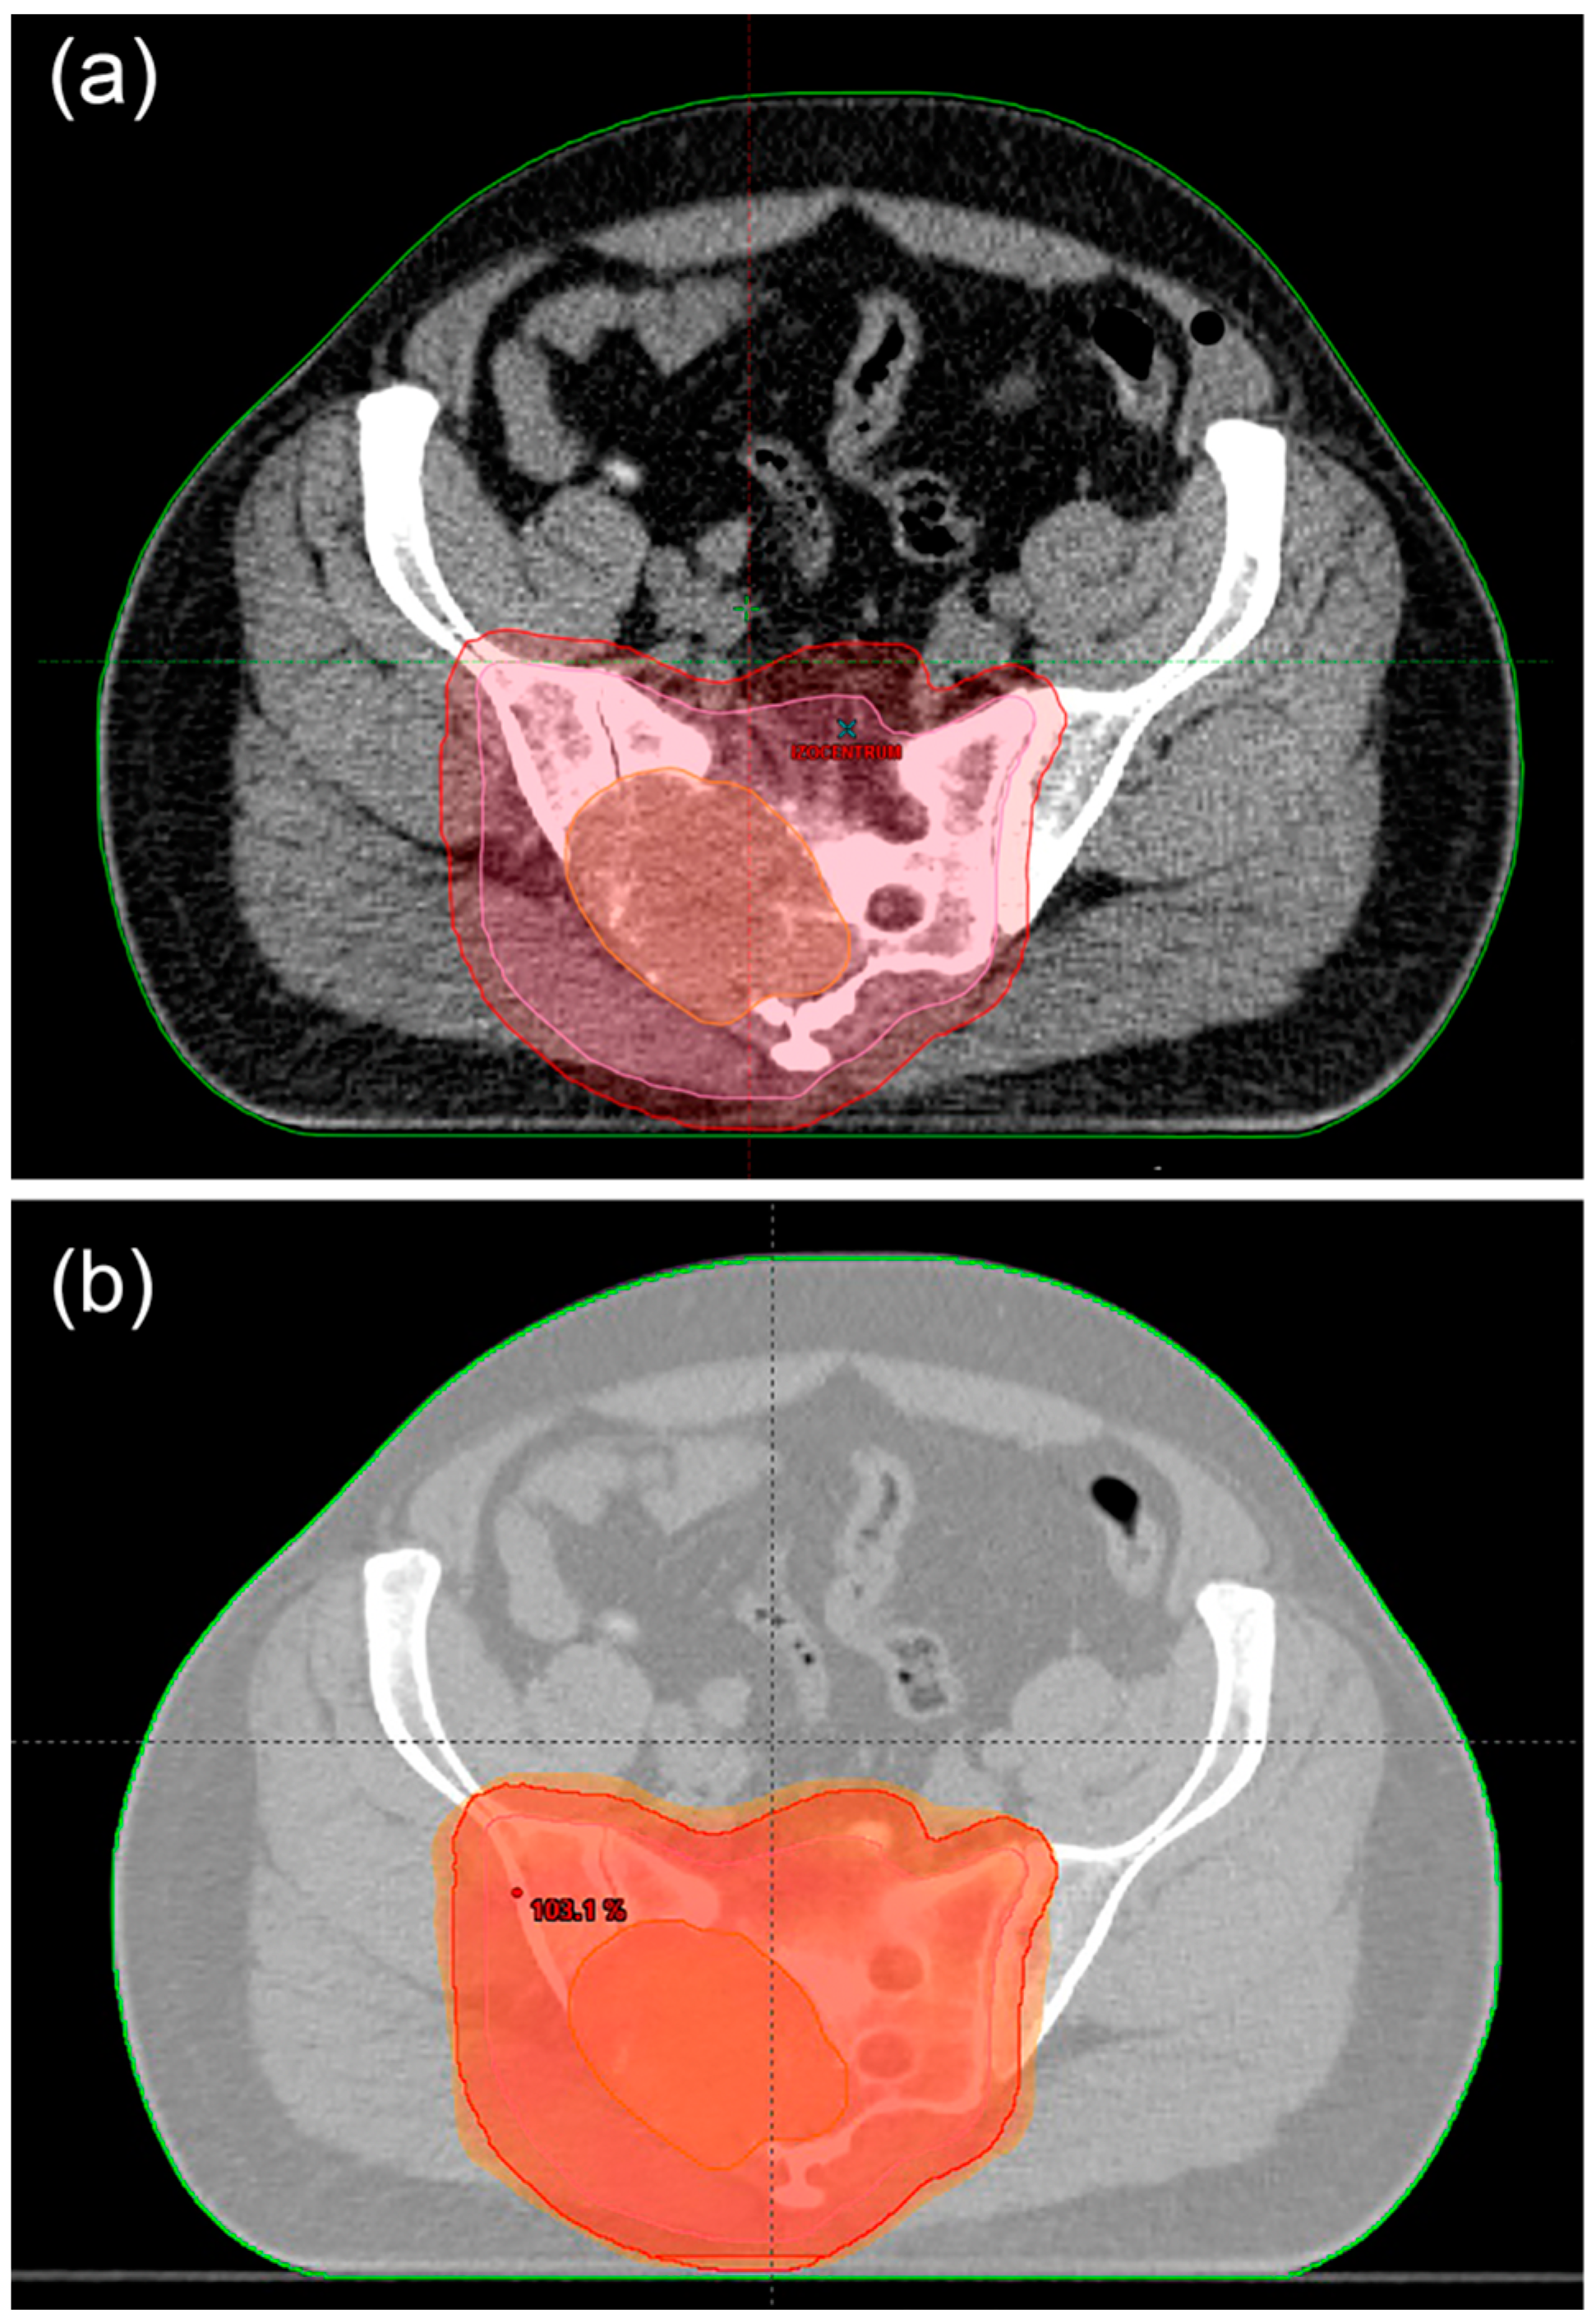

6.3. Ratiotherapy

6.4. Treatment of Metastatic Disease